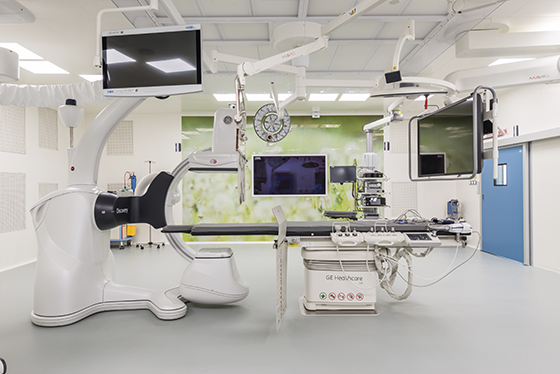

В медицинском центре в Москве проводится МРТ головы с контрастом по доступным ценам. У нас работают опытные специалисты, которые обладают профессиональными навыками для проведения информативной диагностики.

Благодаря современным технологиям удается получить максимально точный результат при обследовании. Экспертное оборудование является гарантией качественной и безопасной диагностики, т. к. позволяет выявить даже скрытые патологические процессы на начальных стадиях прогрессирования. Благодаря этому назначается эффективное лечение, и предотвращаются осложнения.